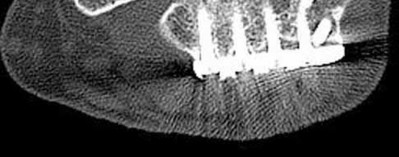

The patient presents with a closed distal third metaphyseal-diaphyseal distal tibia fracture with simple intra-articular extension. Immediate intramedullary nailing along with percutaneous fixation of the articular component provides appropriate restoration of length, rotation and alignment and minimizes the risk of wound complication.

Displaced distal third tibia fractures may be associated with simple intraarticular extension. Operative treatment of intra-articular distal tibia fractures has historically been performed with open reduction and internal fixation. Early open reduction and plate fixation of pilon fractures has been associated with high rates of infection and wound complication. In select patterns with simple articular extension, percutaneous screw fixation and medullary nailing may provide appropriate reduction with minimal soft-tissue risk.

Marcus et al. evaluated the outcomes of immediate intramedullary nailing and percutaneous fixation of simple intra-articular distal tibia fractures (AO/OTA 43 C1 and C2). The authors found excellent rates of union and alignment, however caution against broad application of this technique until more rigorous randomized studies can be performed.

Figures A and B demonstrate a distal third tibial shaft fracture with simple intra-articular extension. The axial and coronal CT cuts in Figures C and D further clarify the articular injury. Illustrations A and B demonstrate a comminuted distal third tibial fracture with simple intra-articular extension. Illustrations C and D are fluoroscopic images of the same injury after intramedullary nailing and percutaneous fixation of the articular component.

A 25-year-old female is involved in a motor vehicle collision. She presents with the isolated injury seen in Figures A through D. Her leg is swollen but her skin is intact. She has no clinical signs of compartment syndrome. Which of the following treatment options will allow for maintenance of fracture alignment and minimize the risk of soft tissue complications?